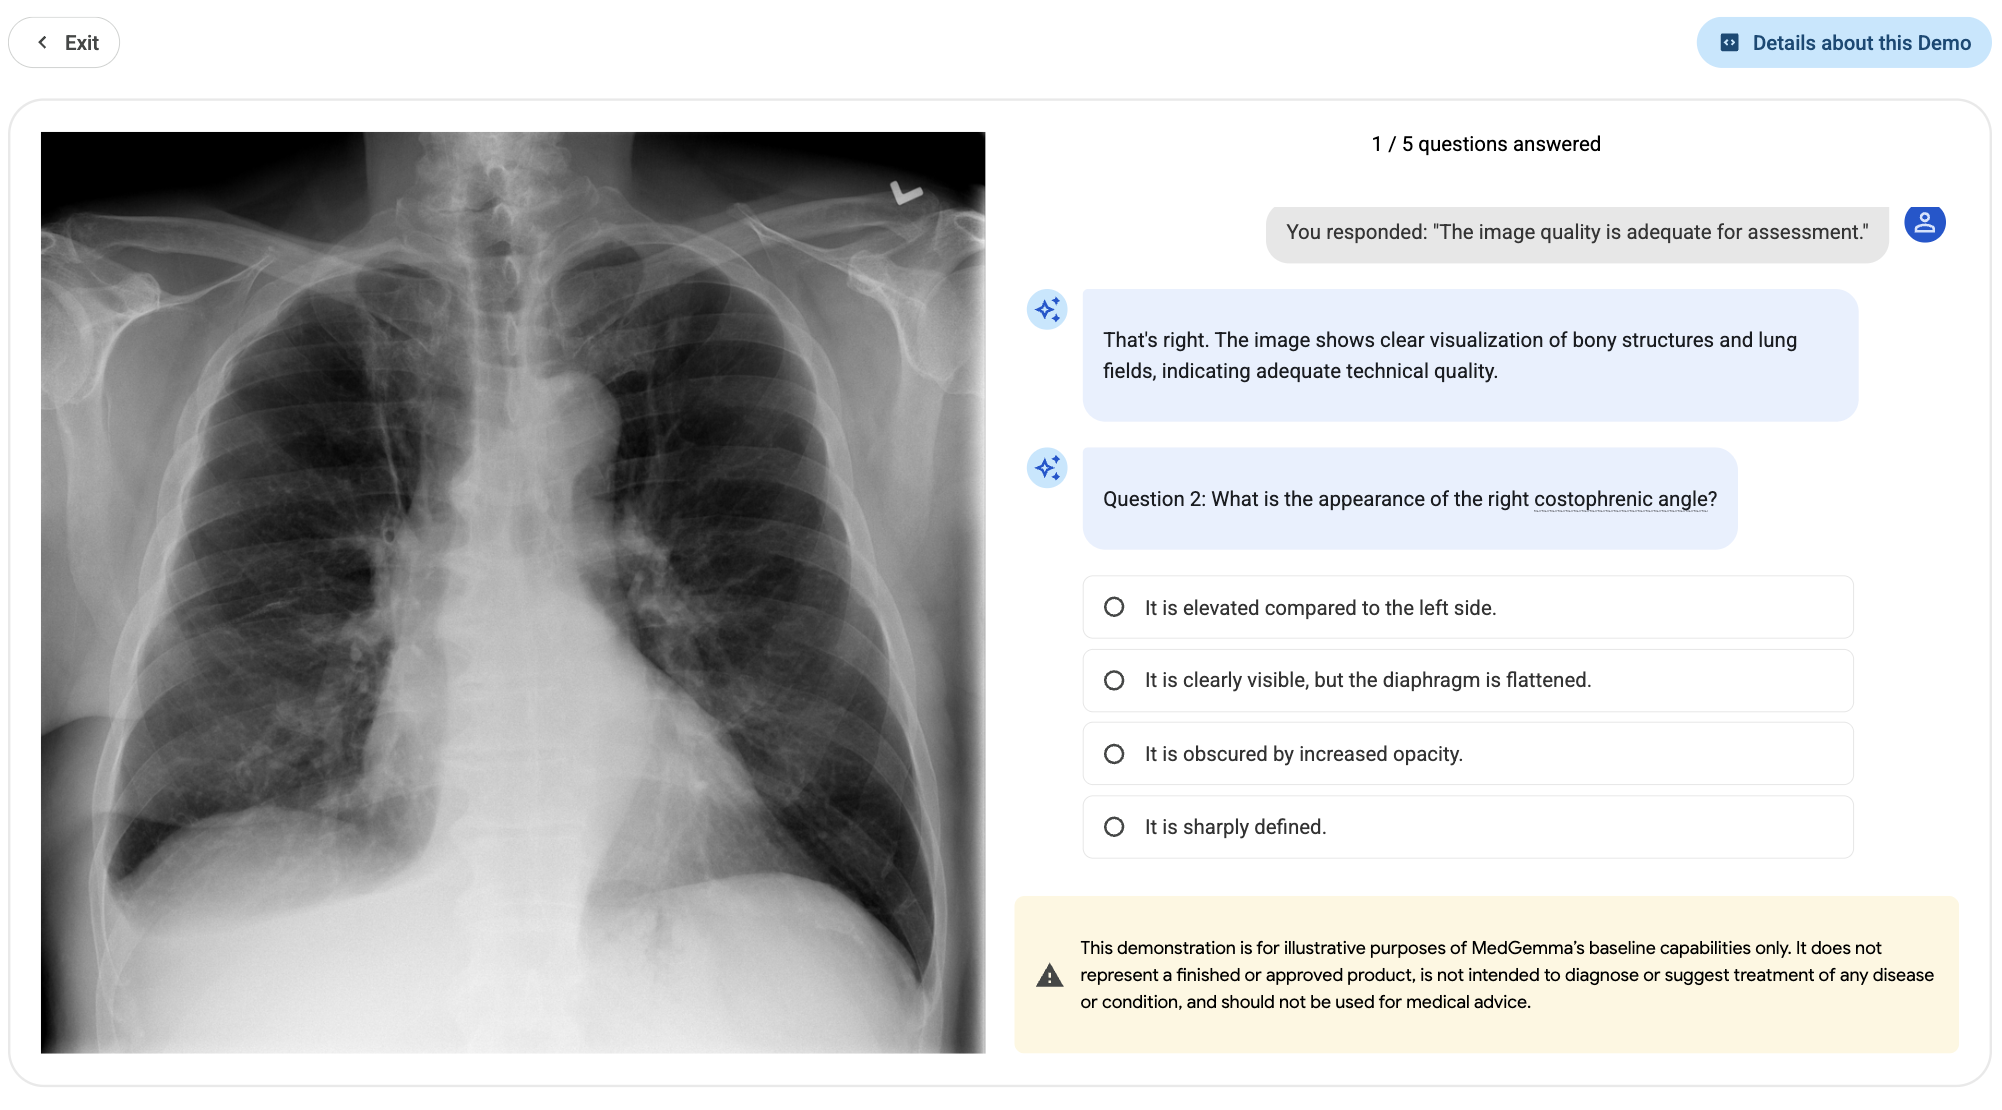

Radiology Image & Report Explainer Demo. Built with MedGemma

A demo showcasing a medical learning experience of CXR image